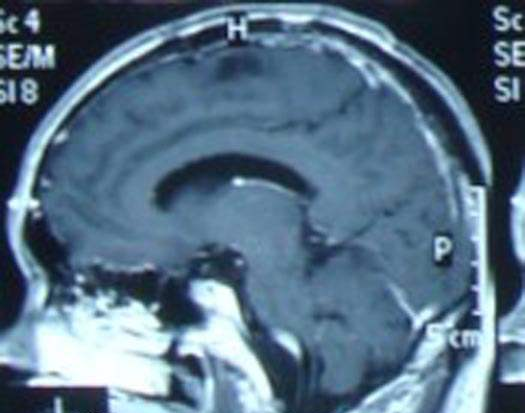

脑部放疗的毒性和海马功能保护,全脑放疗后引起的认知功能损伤更常见的是对学习和记忆功能的影响,患者出现学习能力下降,记忆力减退。成年颅内神经再生能力的主要区域位于侧脑室的室管膜下层和海马齿状回的颗粒细胞下层。

放疗导致海马区域的神经损伤和某种神经传导通路受损,从而引起学习和记忆功能受损。因为海马区域出现脑转移病灶的概率只有约1%,因此通过适形、调强和Tomotherapy等现代放疗技术可以在全脑放疗中对海马区域进行保护(hippocampalsparingradiotherapy)来减少脑部毒性的发生。